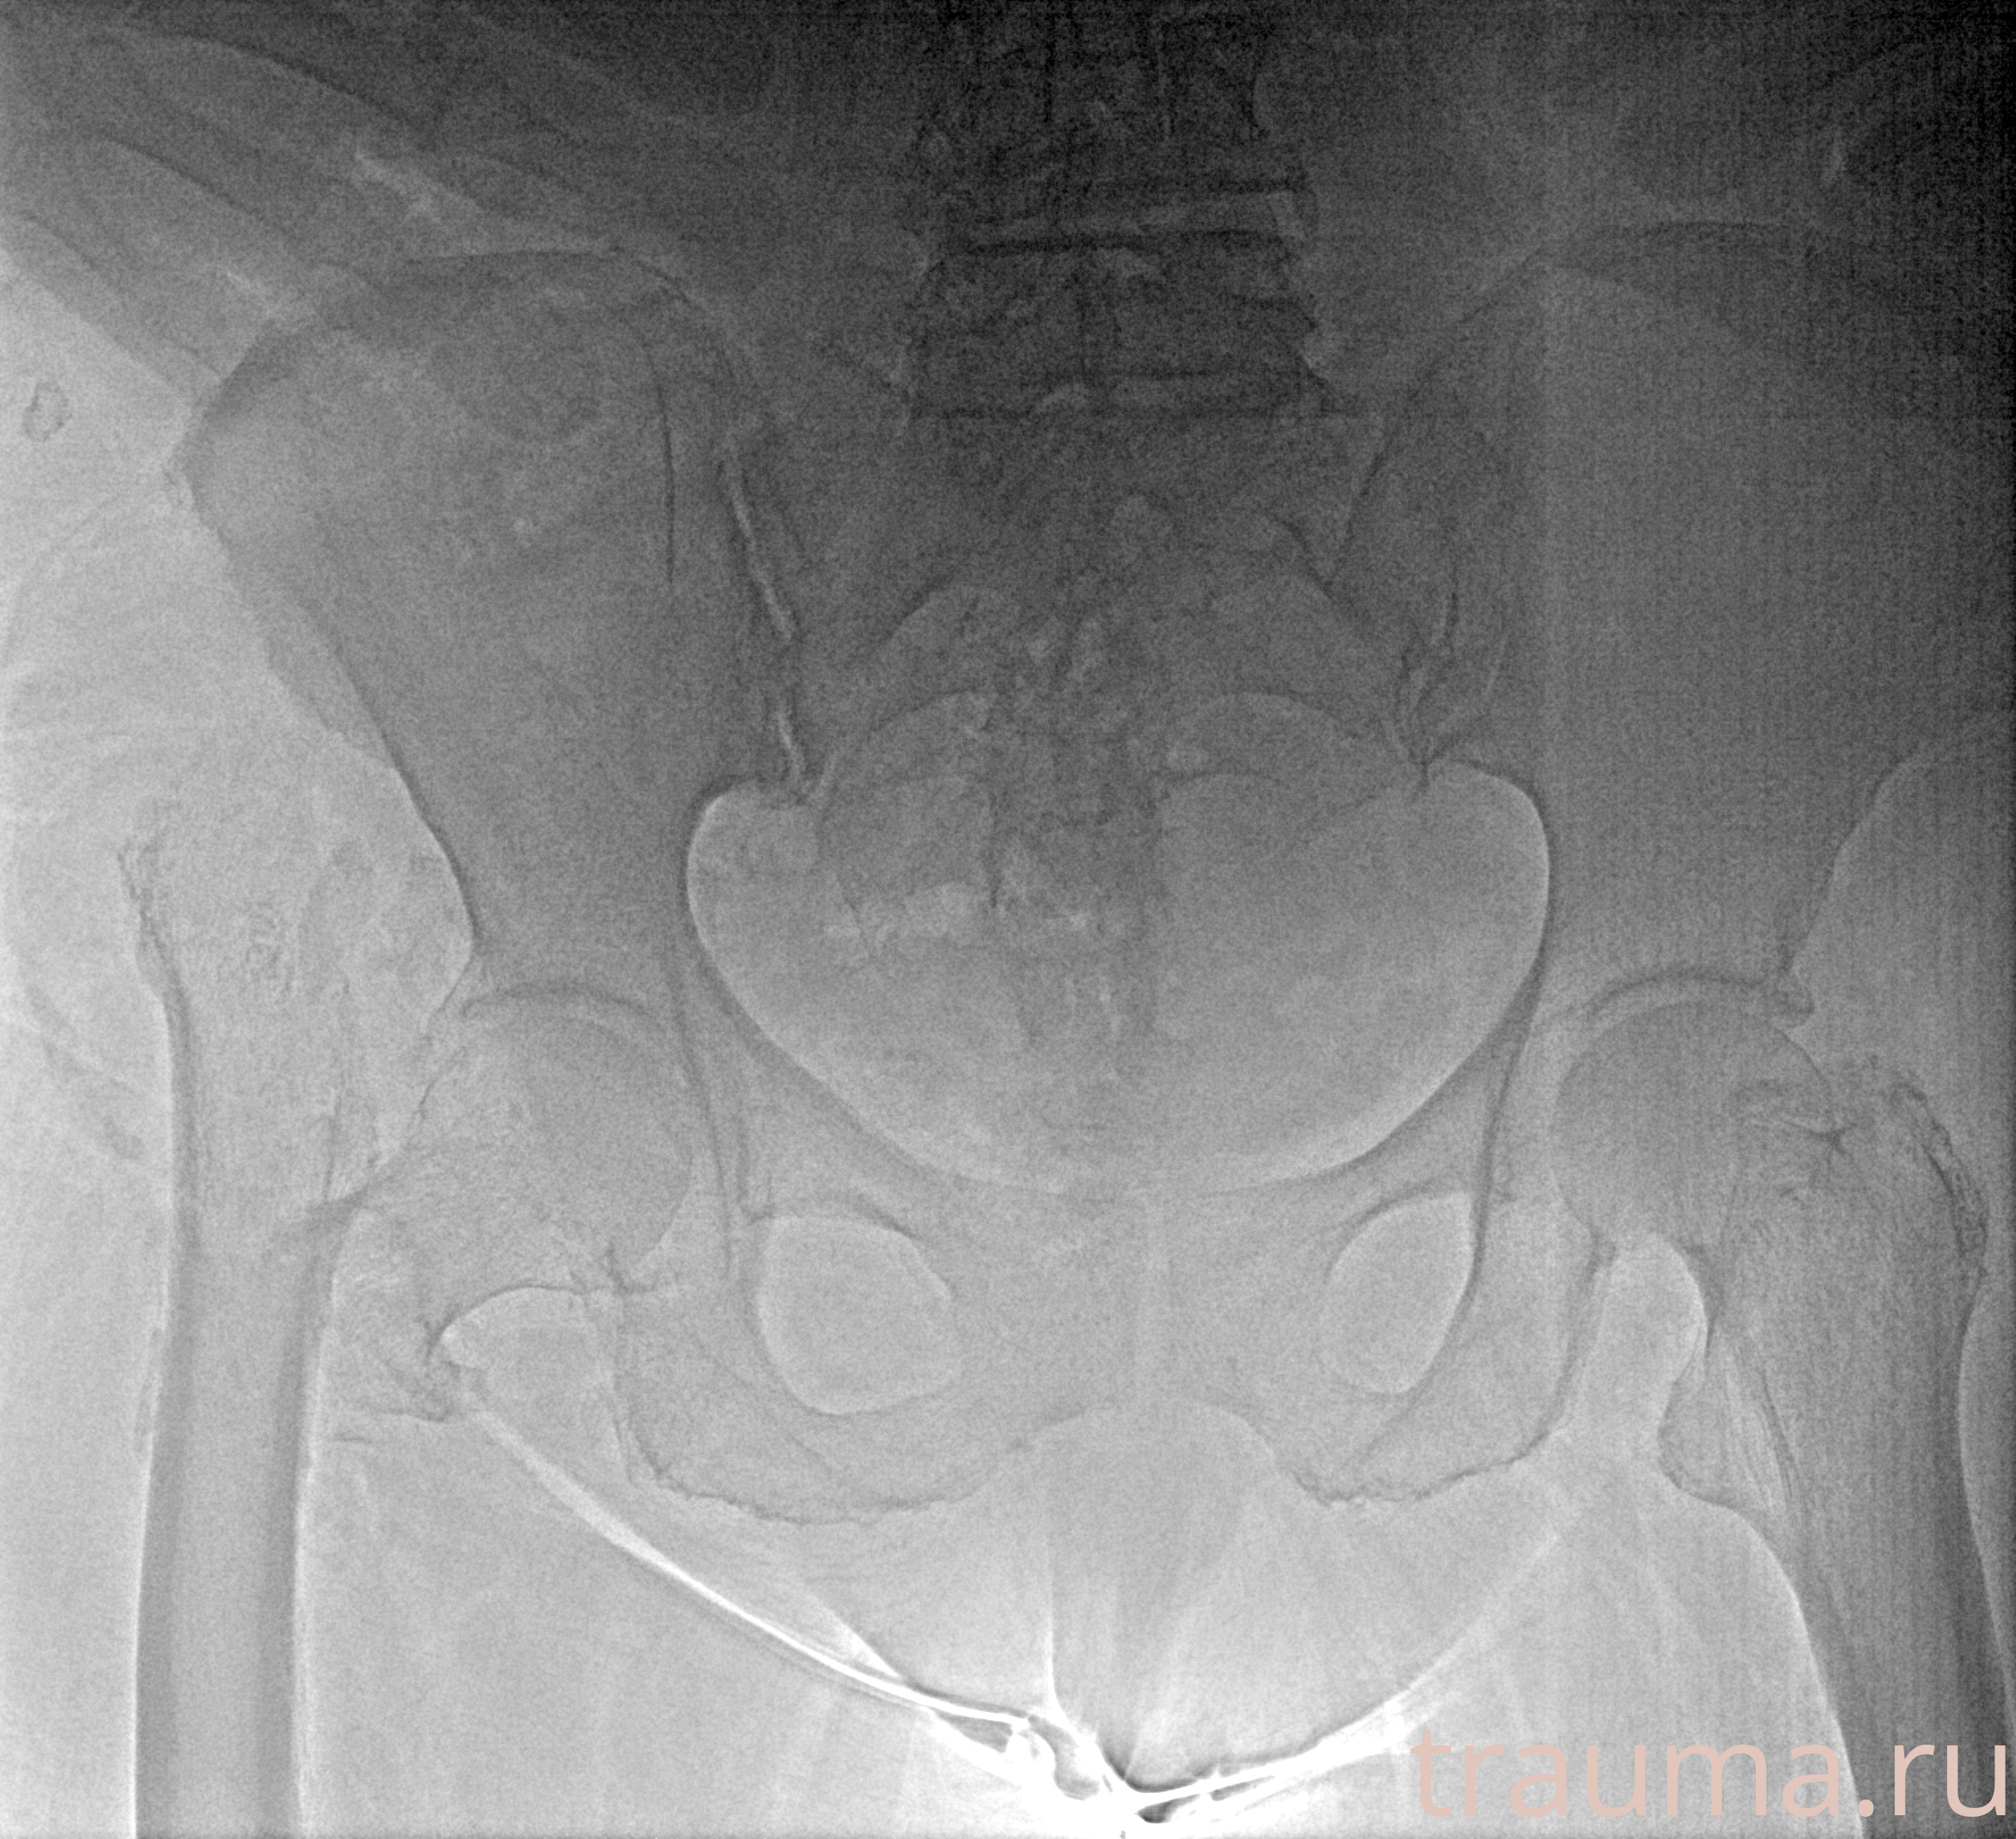

Рентген на дому: по вашему адресу приезжает врач-рентгенолог, травматолог-ортопед с мобильным рентгеновским аппаратом, проводит диагностику травмы или заболевания, делает необходимые рентгенограммы, дает рекомендации по дальнейшему лечению. Получить качественные снимки в домашних условиях возможно благодаря уникальной методике, разработанной МосРентген Центром для института  Склифосовского